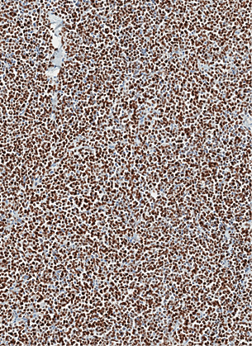

Imunohistocheminio profiliavimo metu nustatyta stipri difuzinė PanCK reakcija visuose komponentuose (3 pav.) ir menka, tačiau definityvi MUC2 žarninio tipo mucinų produkcija (4 pav.) kartu su tipiška KRAS geno 12-o kodono mutacija 2-ame egzone leistų klasifikuoti naviką kaip aukšto laipsnio (blogai diferencijuotą) adenokarcinomą. Ieškant biologinio pagrindo neįprastai naviko morfologijai paaiškinti atliktos papildomos imunohistocheminės reakcijos: Hep-Par1 (neigiama), INI1 (praradimo nėra), BRAF (neigiamas, tikėtina, nemutuotas), PMS2 ir MSH6 (reakcija išlikusi, nėra mikrosatelitų nestabilumo audinyje požymių), visose naviko ląstelių populiacijose patvirtintas jau biopsijoje identifikuotas difuzinis neuroendokrininis fenotipas (100 % Synaptophysin ir 95 % Chromogranin A ekspresija (5 pav.)). Ki67 proliferacinis aktyvumas buvo heterogeniškas ir rabdoidinės išvaizdos komponente siekė 90 proc., o likusiuose buvo perpus žemesnis (6 pav.).

6 pav. Ki67 proliferacinio aktyvumo variacija tarp naviko komponentų, liudijanti fenotipinių skirtumų biologinį pagrindą: 1 – Epitelioidinis ir šeivinis komponentai; 2 – Rabdoidinis komponentas